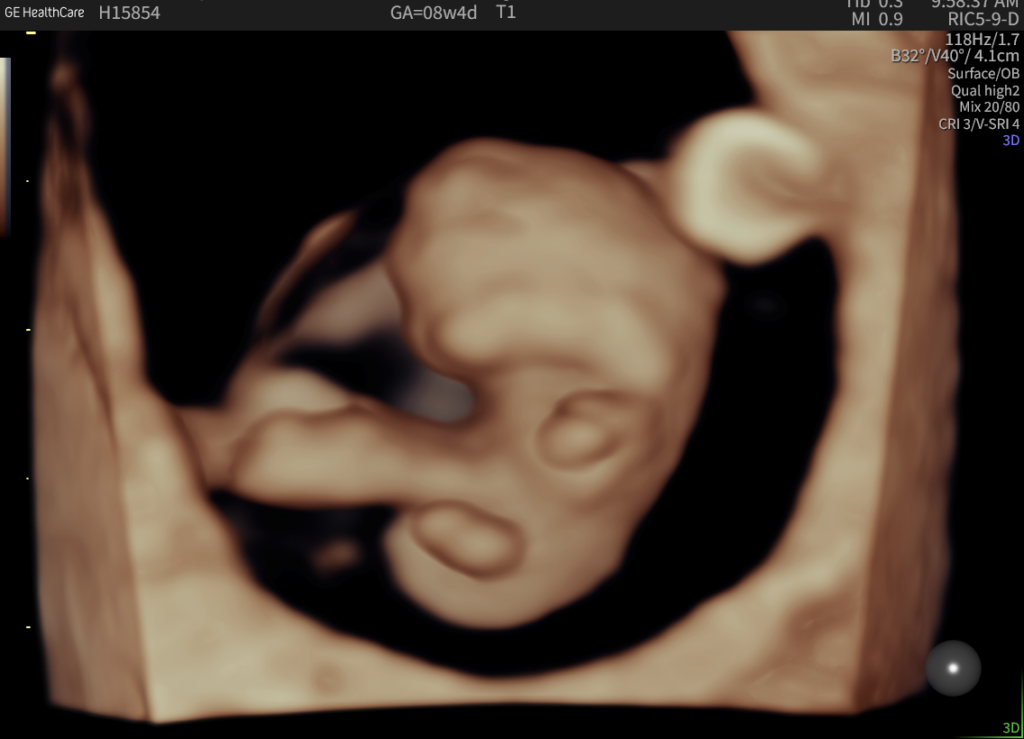

Early Pregnancy Ultrasound

Early Pregnancy Scan

What An Early Pregnancy Ultrasound May Be Able To Detect

• Determine how far along you are and provide an estimated due date.

• Confirm that your pregnancy is progressing as expected and that the baby is in the right place.